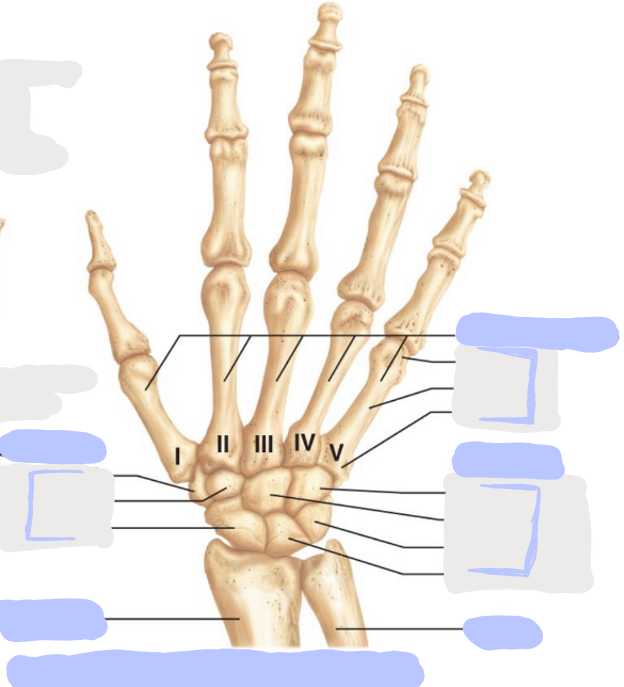

What is this picture of?

Posterior View of the Right Hand

What is here?

Where is the Ulna?

What is here?

Where is the Radius?

What is here?

Where are the Metacarpals?

What is here?

Where are some of the Carpals?

What is here?

Where are some of the Carpals?

How many carpals are there?

8

How many metacarpals are there?

5

How many phalanges are there?

14